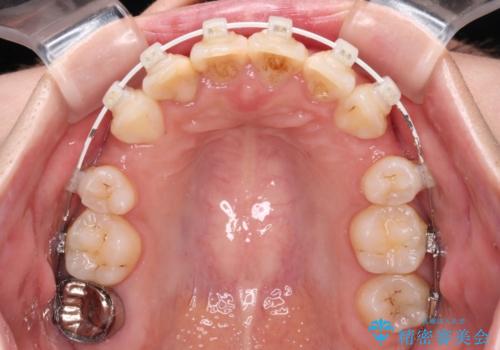

デコボコと深い咬み合わせ ワイヤー装置での抜歯矯正

- 矯正装置

- 審美装置

下顎の叢生を解消するために抜歯が必要であり、奥歯の咬み合わせや口元の印象から、上顎も同様に抜歯と判断し、上下左右の第1小臼歯4本抜歯してワイヤー装置にて矯正治療を行うこととしました。

咬み合わせが深く、そのままでは上顎の抜歯スペースが閉じきらない可能性があったため、治療初期から深い咬み合わせを改善させるように試みました。

実際にはなかなか改善されず、当初予定よりも治療期間がやや長期化してしまいました。